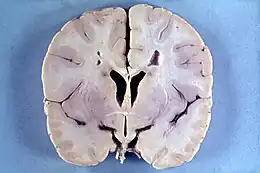

La maladie d'Alexander est une maladie rare de la substance blanche du cerveau. Elle survient le plus souvent dans les premières années de vie (forme infantile) mais parfois plus tard (forme juvénile) mais des formes néonatales ou de l'adulte existent.